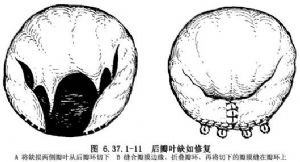

②瓣叶缺如:后瓣叶缺损或局限发育不良将该处瓣膜边缘矩形切齐,对缘缝合,相应部位的瓣环折叠。Carpenrtier 1988年设计的修复方法是将瓣缘切齐后,将后瓣沿两侧瓣环上切开,对缘缝合,相应瓣环折叠后,再将后瓣缝在瓣环上,称为滑行瓣叶手术方法(sliding leaflet techique)(图6.37.1-10)。前瓣孔洞是局限性瓣叶缺损,可直接心包补片修补(图6.37.1-11)。